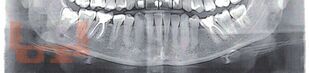

Эффективность трансдермальной системы гель «Поликатан» и «Тизоль» в комплексном лечении воспалительных заболеваний пародонта

В учебном пособии освещаются вопросы актуальности воспалительных заболеваний пародонта в стоматологии и социуме, аспекты этиологии и принципов лечения пародонтопатологий. Особое внимание уделяется применению геля «Поликатан» и «Тизоль» в комплексном лечении воспалительных заболеваний тканей пародонта.